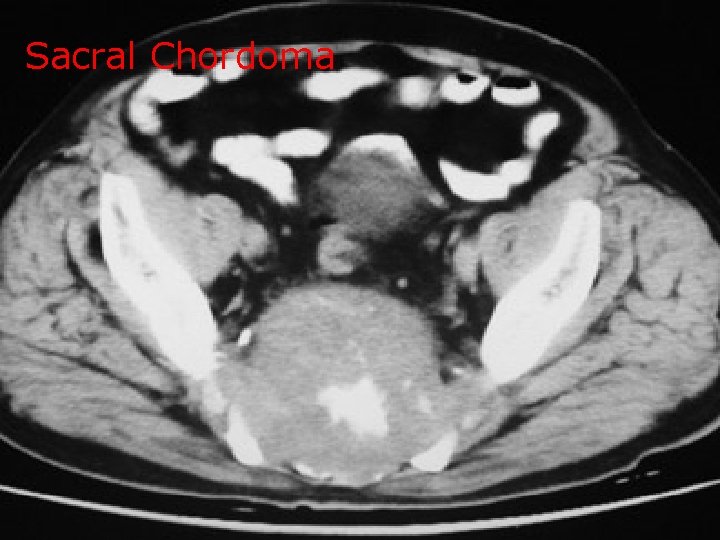

Sacral Chordoma